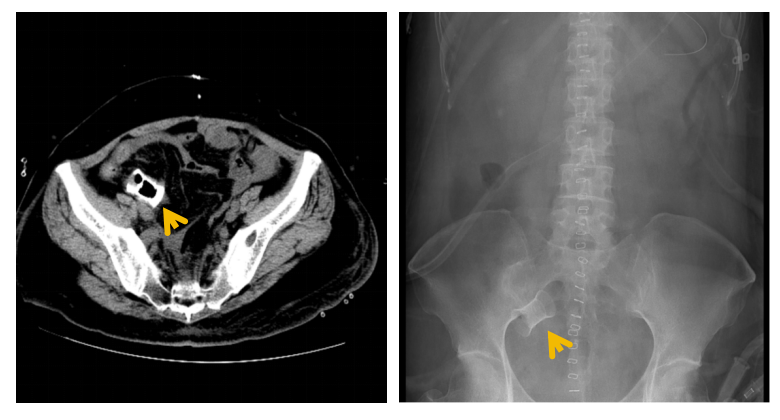

图3:术后盆腔CT及腹部平片可见完整小肠支架影子(箭头)

在妇科肿瘤外科、营养科及护理团队的通力合作下,患者邓女士术后恢复迅速,顺利进食,转流管引流通畅。术后复查显示支架位置良好,肝肾功能等指标稳定,并于术后第三周如期开始了首次静脉化疗。术后第四周,影像学证实支架已完全降解,转流管成功拔除,患者进食半流质后一切正常,吻合口愈合良好(如图4)。